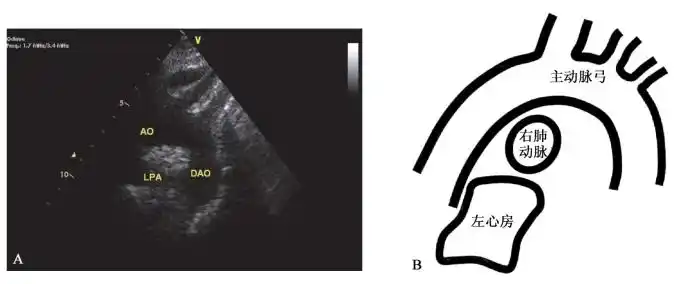

二维超声心动图检查技术